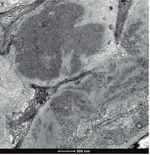

• Microscopia electrónica: un glomérulo con distorsión general de la arquitectura con engrosamiento de las paredes capilares y expansión mesangial por la presencia de abundantes depósitos de fibrillas localizadas tanto en el mesangio como en las paredes capilares, que se distribuían aleatoriamente, y que eran de mayor tamaño que las de amiloide, con un grosor medio que oscilaba entre 20-25 nm (figs. 2 y 3). Ante los hallazgos de las fibrillas se solicitó rojo Congo, que fue negativo, por lo que se descartó la amiloidosis.

Figura 2. Microscopio electrónico: depósito de fibrillas.

Figura 3. Microscopio electrónico: depósito de fibrillas.